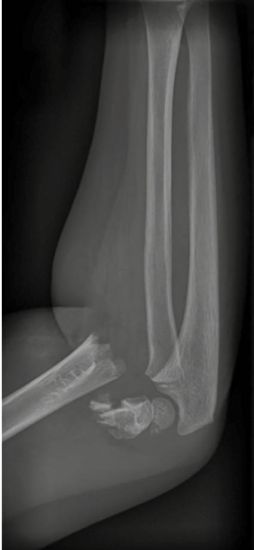

Die Röntgennativaufnahmen des rechten Ellenbogengelenks in 2 Ebenen zeigten eine dislozierte suprakondyläre Humerusfraktur (Abb. 1, Seite 16). Doppler-sonografisch war eine Durchblutungsstörung der A. radialis nachweisbar mit reduzierten Pulskurven. Das stationäre Aufnahmelaborprofil ergab eine auffällige Leukozytose von 14,3 Gpt/l.

Abb. 1: Die initiale Röntgen-Untersuchung des Ellenbogengelenks seitlich zeigte eine dislozierte suprakondyläre Humerusfraktur

(Foto: Klinik für Radiologie und

Nuklearmedizin, Universitätsklinikum Magdeburg A.ö.R.)